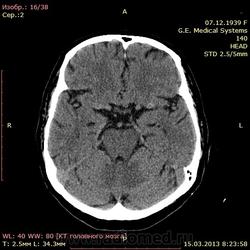

А как по мне, то тут геморрагический инсульт. Есть дислокация срединных структур слева.

Геморрагический инфаркт левой височной доли (в проекции таламуса слева) как правильно по локализации сам не знаю, скорее все таки таламус, со смещением срединных структур вправо, третий и левый боковой желудочек частично компримированы, формируется зона перифокального отека

тут либо геморрагический инсульт с перифокальным отеком, либо ишемический инсульт с геморагическим пропитыванием. Как их различить? Что скажут опытные коллеги?

Типичное медиальное кровоизлияние (в таламусе, медиальнее внутренней капсулы), уже не совсем свежее, плотность уже более низкая и зона отека приличная.

КТ признаки кровоизлияния в базальных ядрах, отделах с выраженными признаками перифирического отека. Про давность - сами пусть спросят , но скорее не свежак, до 5-6 дней.

Описывайте как геморрагический инсульт с объемным действием (смещением) на срединные структуры мозга. Померяйте плотности для оценки стадии. А различить на КТ две обговариваемые формы думаю нельзя. Разве что при пропитывании не будет такой четкой динамики изменения плотности очага. В литературе не встречал.